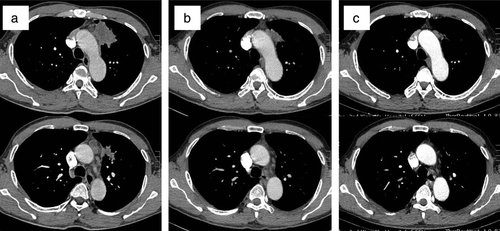

患者立即开始口服奥西替尼(80 mg,每日一次)。没有出现明显的副作用(AEs)。治疗1个月和3个月后的CT扫描显示肺部病变和淋巴结明显减少,疗效评估为部分缓解(PR)。

图注:(a)诊断时,考虑左上叶肿块为原发肿瘤,纵隔肿块为5、6组淋巴结转移。(b)奥西替尼治疗1个月后,原发肿瘤和淋巴结均缩小。(c) 奥西替尼后3个月,原发肿瘤明显缩小,纵隔肿块消失。